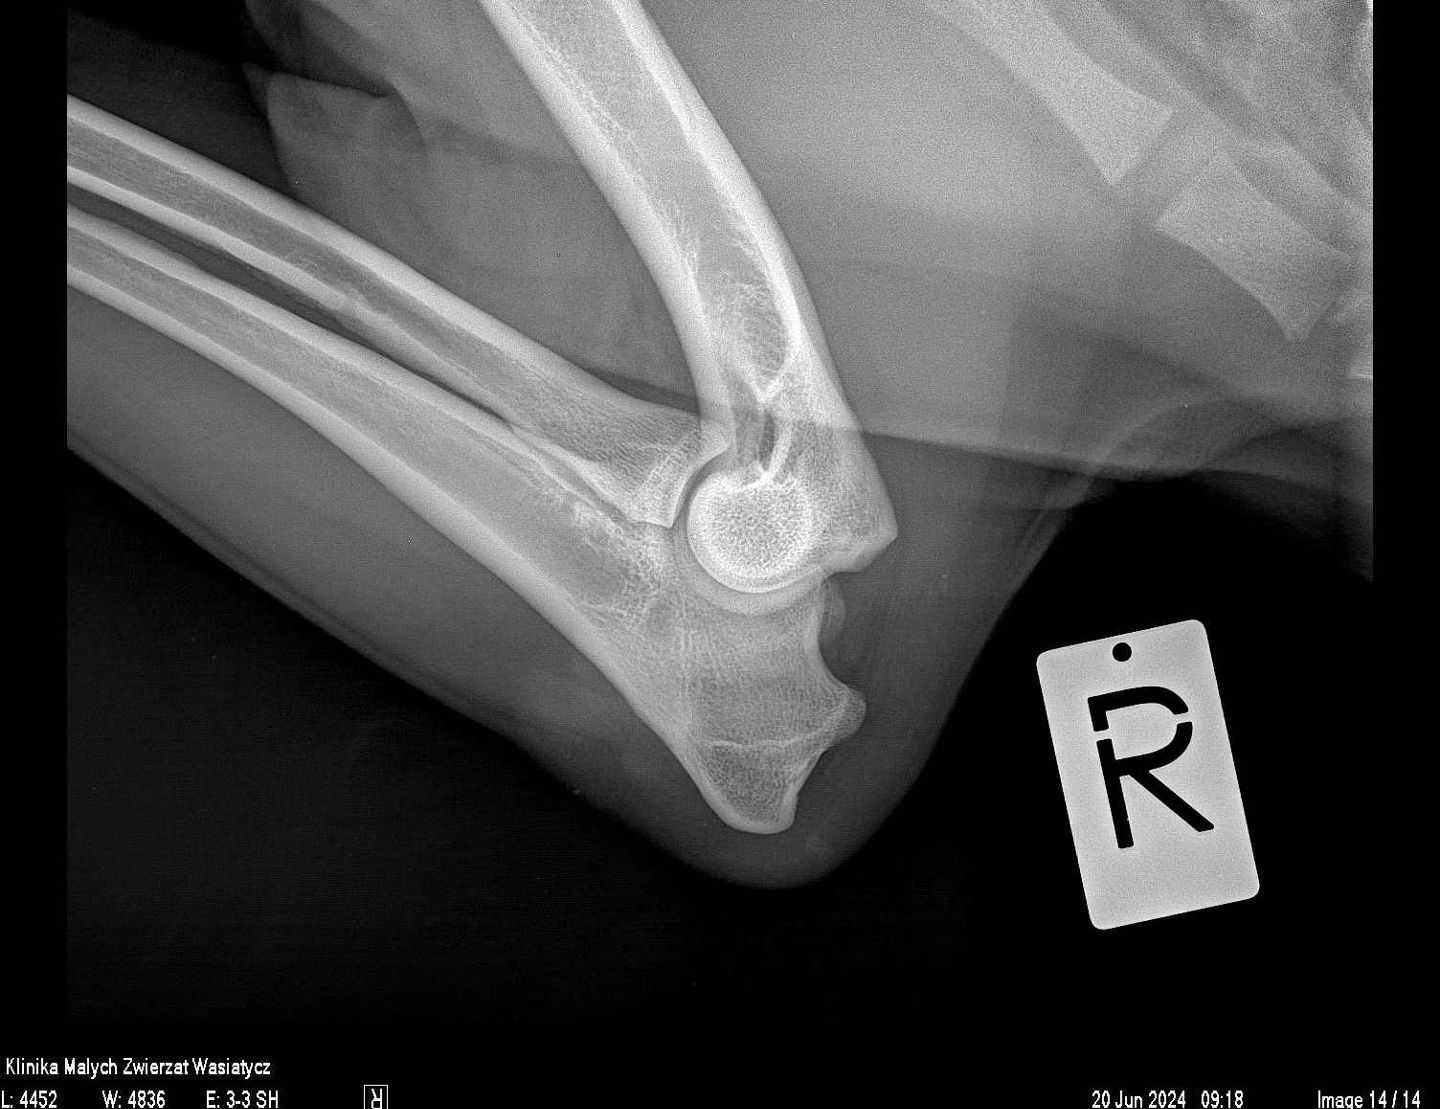

W naszej klinice pracownia rentgenowska stanowiła zawsze bardzo ważne miejsce diagnostyczne. Jako placówka specjalizująca się w ortopedii staramy się zapewnić najwyższą jakość zdjęć rtg, zarówno w zakresie dokładności ułożeń jak i parametrów ekspozycji.

Obecnie, w naszej pracy wykorzystujemy najwyższej klasy sprzęt rentgenowski hiszpańskiej firmy Initech, który został specjalnie skonfigurowany zgodnie z naszymi potrzebami. Jest to również system radiologii bezpośredniej.

Rocznie w naszej klinice wykonywanych jest prawie 20 000 zdjęć rentgenowskich. Każde z nich jest wykonywane przez stale doskonalących się specjalistów, analizowane przez wysokiej klasy lekarzy weterynarii, w tym również specjalistów radiologów. Wszystko to sprawia, że badanie rtg dostarcza maksymalną ilość informacji, która potrzebna jest w procesie diagnostycznym.